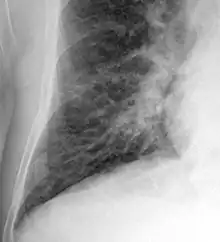

Chest X-rays are frequently used to aid in the diagnosis of CHF. In a person who is compensated, this may show cardiomegaly (visible enlargement of the heart), quantified as the cardiothoracic ratio (proportion of the heart size to the chest). In left ventricular failure, evidence may exist of vascular redistribution (upper lobe blood diversion or cephalization), Kerley lines, cuffing of the areas around the bronchi, and interstitial edema. Ultrasound of the lung may also detect Kerley lines.[72]

Congestive heart failure with small bilateral effusions

Kerley B lines